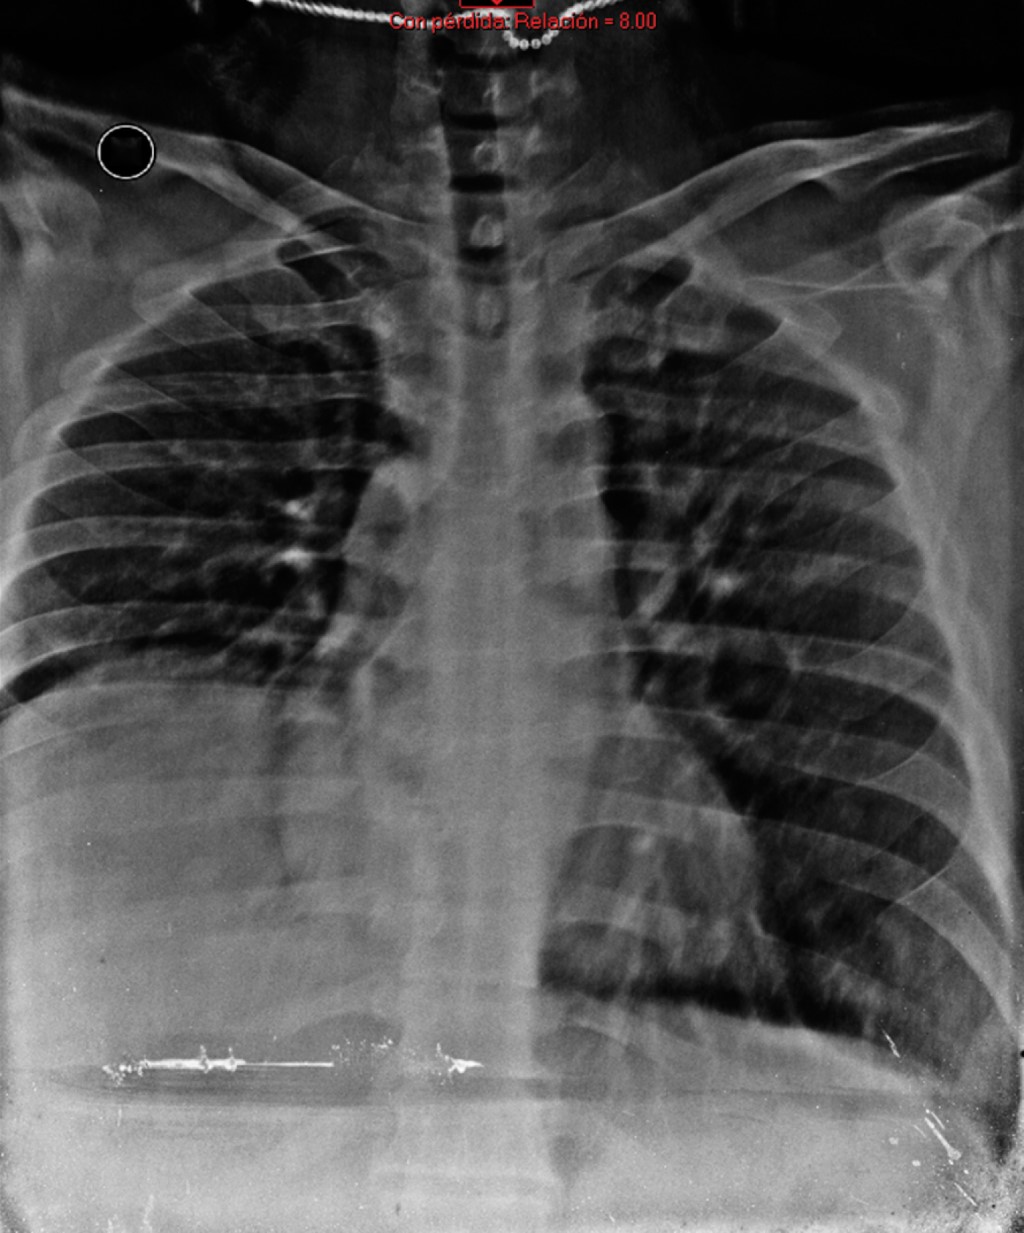

A causa del hallazgo tomográfico el paciente permaneció en vigilancia, a las 48 horas de su estancia intrahospitalaria se efectuaron controles de laboratorio y de imagen (Figura 4), sin cambios significativos con respecto a su ingreso. No se evidenció conversión hemorrágica de quiste hepático. A su egreso, se observaba paciente con mejoría sintomatológica, sin complicaciones.

Figura 4